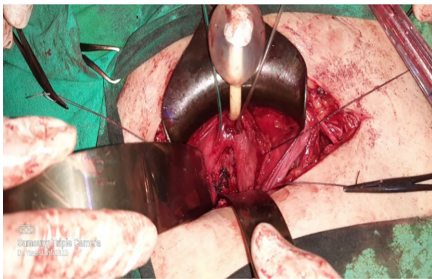

手术采用经典的Pfannenstiel切口,术中发现膀胱后壁实性肿块,与周围结构分界清楚。团队实施了精准的肿块切除术,完整保留了膀胱三角区等重要结构。